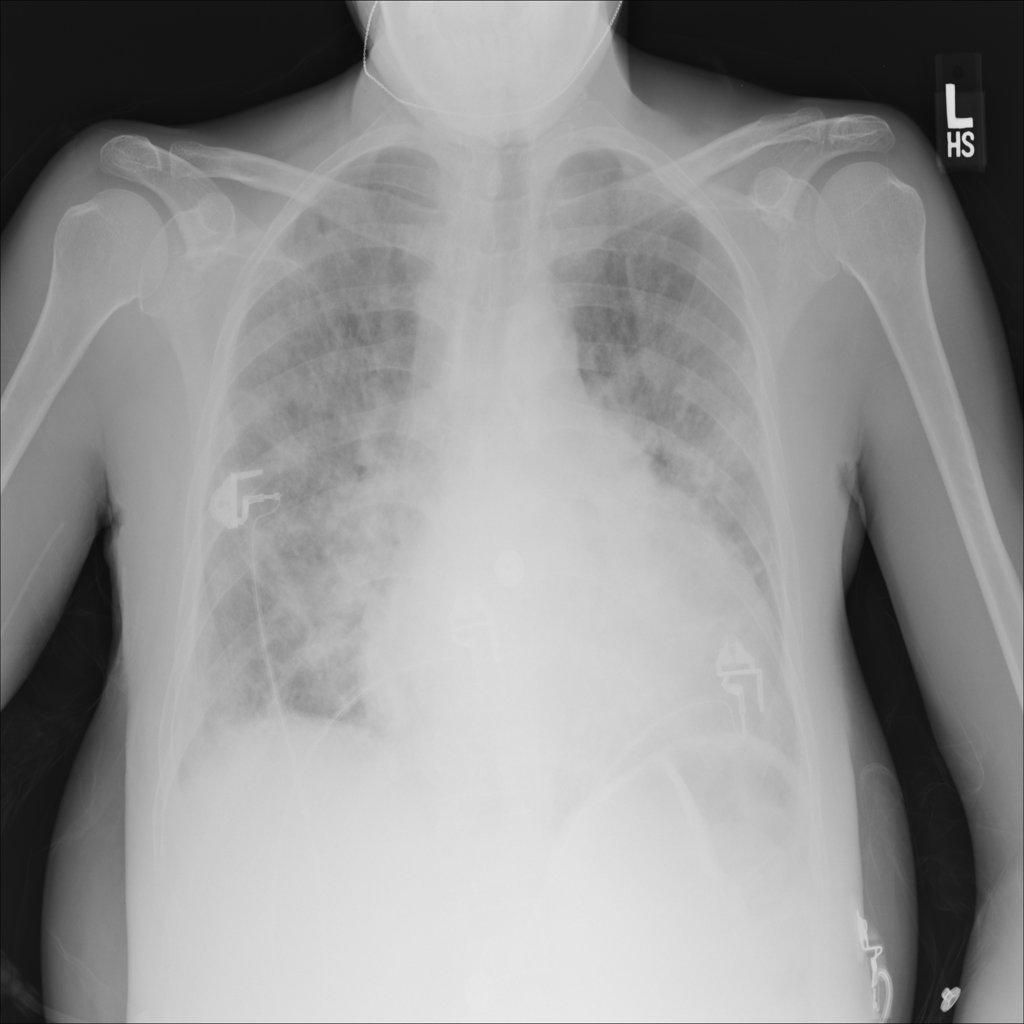

PAT-C0E5 · IMG-015Pneumonia

PAT-C0E5 · IMG-015

AP